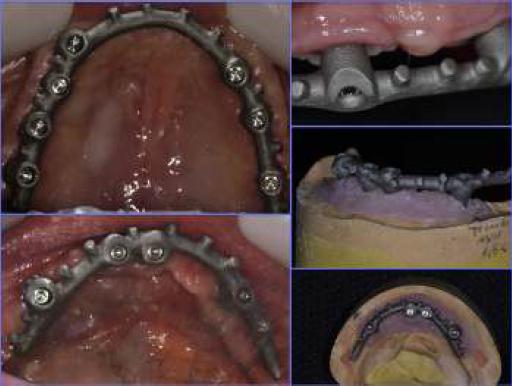

Una vez transcurrido el tiempo necesario para la oseointegración (2 meses en el maxilar inferior y 6 en el superior) se conectan los implantes (ISQ entre 65 a 70 en todos los implantes en mediciones perpendiculares entre sí para cada implante, a excepción de implante en relación a 2,5 que solo logra un ISQ de 45) utilizando pilares cónicos, rectos en los implantes mediales y con angulación de 30◦ en los implantes distales. Además, se confeccionan las prótesis provisorias fijas sobre los implantes, indicando a la paciente las técnicas de cepillado y mantenimiento correspondiente. En el momento de la conexión se pierde un implante en relación con la pieza 2,5, situación que al no afectar en el pronóstico del tratamiento se decide no insistir en su repocisión. Una vez estabilizados los tejidos blandos (fig. 3) se realiza la toma de impresión con silicona por adición Panasil Putty e Initial Contact Light® (Kettenbach GmbH & Co.KG, Eschenburg, Alemania) con cubeta funcional mediante la técnica de cubeta abierta, ferulizando los transfers de impresión con resina bis-acrílica Luxatemp® (DMG, Hambrug, Alemania). Además, se toma impresión a los provisionales y se realiza toma de registros. Los modelos de trabajo y los obtenidos de las prótesis provisorias fueron escaneados en el laboratorio para realizar el diseño asistido por ordenador (CAM) de las subestructuras metálicas para las rehabilitaciones protésicas (fig. 4), utilizando como referencia las prótesis transitorias, respetando así los espacios protésicos necesarios y obtener, de esta manera, una rehabilitación funcional y estética. Las subestructuras diseñadas se confeccionaron mediante sinterizado láser, lo que permitió controlar de forma precisa el diseño de los socavados y perlas de retención para acrílico (fig. 5). La prueba de las barras en boca muestra un ajuste pasivo de estas, lo que se corrobora con la toma de radiografías panorámica y periapicales, observando el correcto asentamiento protésico tanto maxilar como mandibular (fig. 6). Una vez verificado el ajuste pasivo de las subestructuras, se continúa con la confección de las prótesis híbridas, con el recubrimiento acrílico de las barras, logrando resultados satisfactorios, tanto funcionales como estéticos, al devolver el soporte labial y reponer los elementos dentarios perdidos (figs. 7 y 8). Una vez finalizadas las prótesis estas se torquean a 15 N y se sellan las chimeneas con teflón y resina compuesta (Permaflow Pink®, Ultradent Walladent y Amellogen Plus®, Ultradent Walladent, EE. UU.) (fig. 9).

Existen distintas alternativas para la confección de la subestructura de las prótesis híbridas, tanto en materialidad como en su técnica de confección. En el presente caso clínico se optó por su fabricación en aleación de cromocobalto, debido a sus propiedades mecánicas satisfactorias y menor costo. La confección mediante sinterizado láser permitió la obtención de las subestructuras en una pieza, sin limitaciones en su diseño, relacionado con el tamaño de cubos o fresas utilizadas para la confección asistida por ordenador, con un costo menor al utilizar menos materia prima. Los niveles de corrosión en la aleación de Cr-Co por sinterizado láser encontrados por Xin et al. son bajos y similares a los conseguidos con técnica de colado, por lo que cumplen con las necesidades clínicas. Además, se obtuvo una superficie más homogénea y, por lo tanto, con mayor dureza y en un menor tiempo en comparación con la técnica de colado convencional13,14.